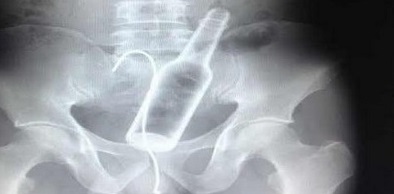

العثور على زجاجة وسلك في بطن مريض

اكتشف أطباء صينيون زجاجة راكدة في بطن مريض وذلك بعد أن قاموا بعمل أشعة سينية له حيث كان يشكو من آلام مبرحة في المعدة.

وذكرت صحيفة "ميرور" البريطانية، أن المريض، الذي لم يرغب في الكشف عن هويته، أدلى بملابسات وصول الزجاجة إلى أمعائه، بعد أن أطلعه الأطباء على صور الأشعة، موضحاً أنه جلس على الزجاجة عن طريق الخطأ، ثم حاول استخراجها بسلك عن طريق الفم لكنه لم ينجح، وخاصة بعد أن سقط السلك في بطنه أيضاً مما دفعه إلى زيارة طبيب.

وخضع المريض إلى جراحة لاستخراج السلك والزجاجة، التي تسببت له في بعض الجروح الداخلية بالأمعاء.